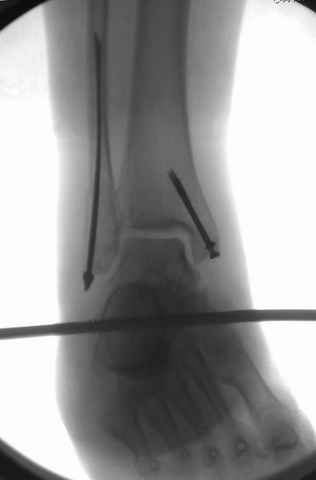

Второй случай сделан из одного разреза

Дж

Pilon fracture:

Дистракция в аппарате или на вытяжение результат - лигаментотаксис, посмотреть бы, как сегодня расположены отломки.